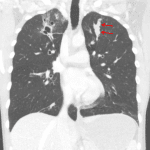

- Bilateral upper lobe predominant tubular and cystic structures

- Calcified nodule in the right upper lung

- Allergic bronchopulmonary aspergillosis (ABPA)

Bilateral upper lobe predominant bronchiectasis and bronchial impaction compatible with sequela of chronic infection/inflammation including allergic bronchopulmonary aspergillosis.